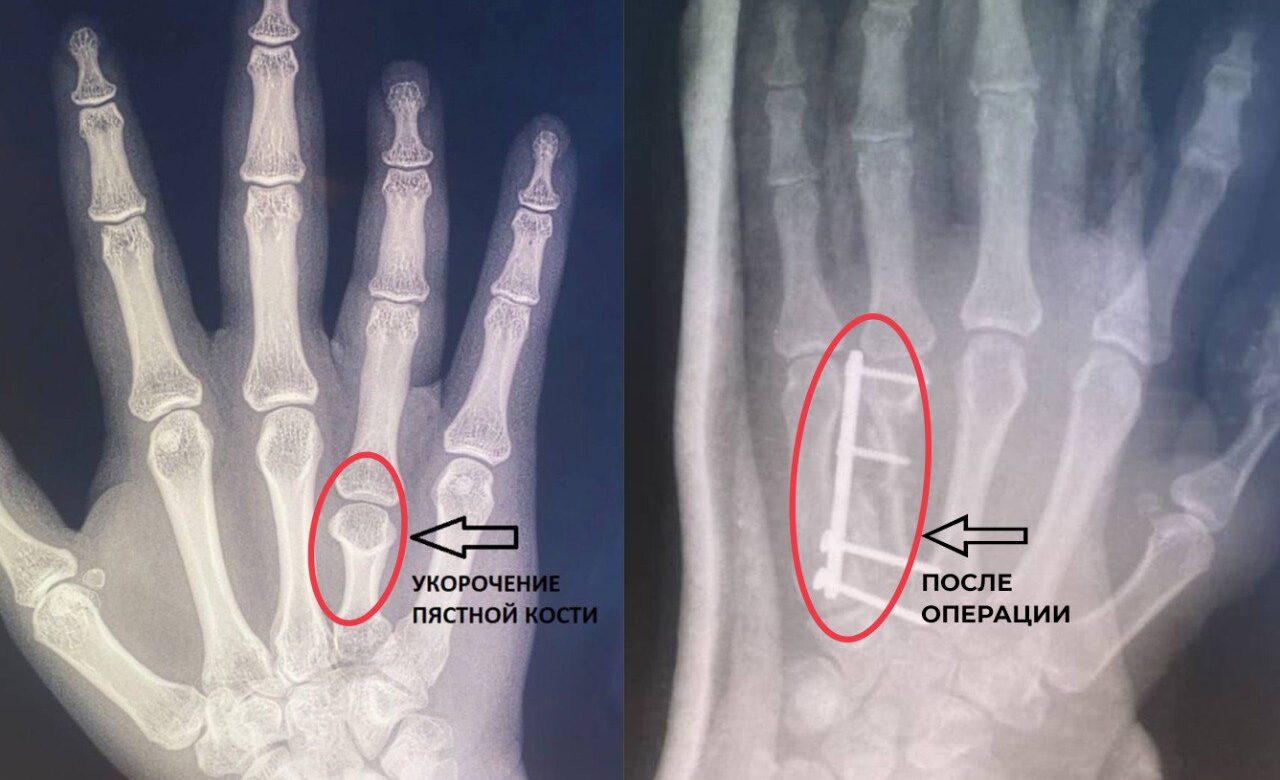

Владимирские врачи из областного центра спецмедпомощи сделали жизнь одной девушки проще, удлиннив ей безымянный палец на правой руке. До этого пальцем было невозможно двигать в полном объеме, рассказали в пресс-службе Минздрава.

У пациентки выявили брахиметакарпию – врожденная патология, проявляется укорочением одной или нескольких пястных костей, из-за уменьшается длина пальцев. Дефект опаснее, чем кажется, ведь он становится причиной проблем с мелкой моторикой. Чаше от заболевания страдают девочки.